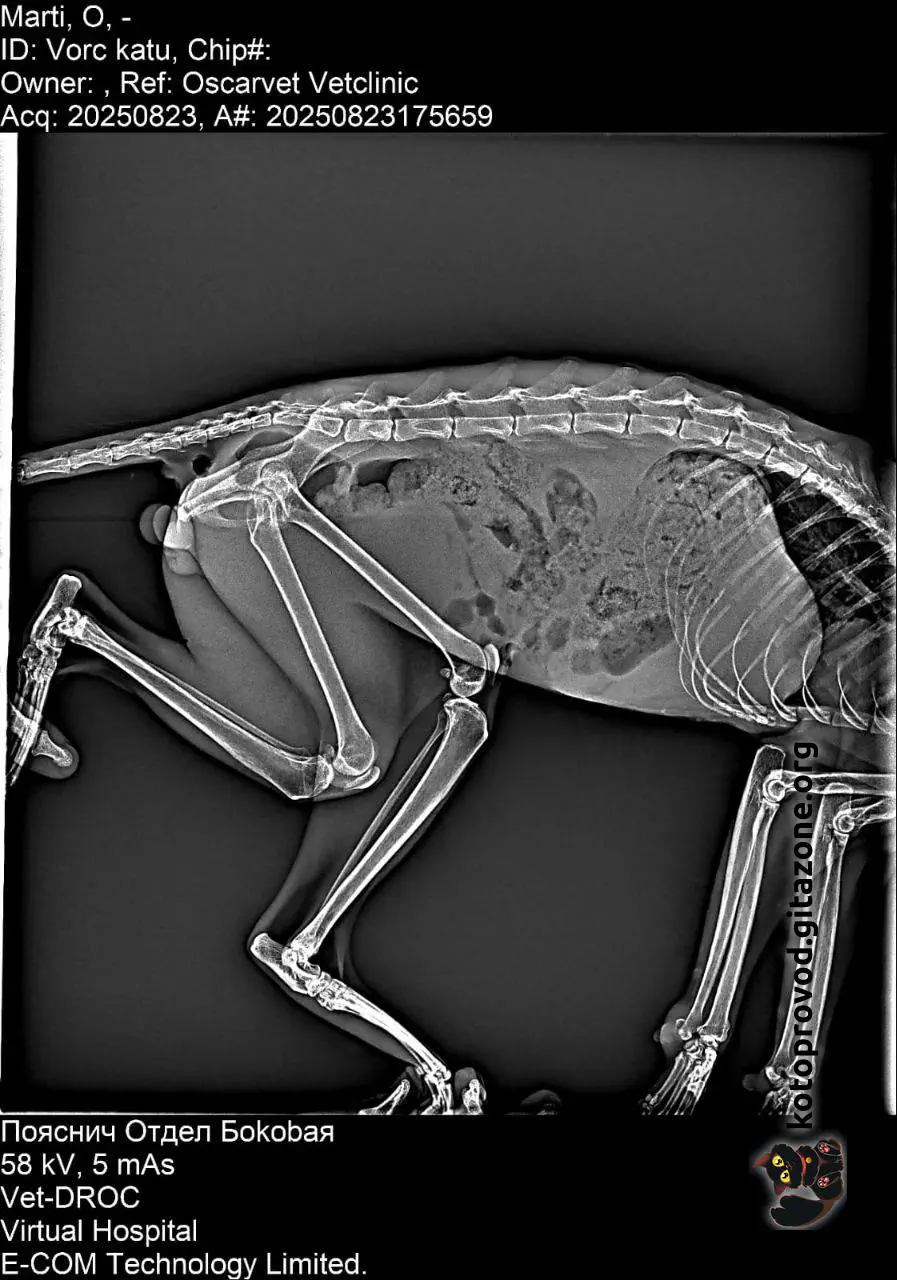

Martini (white-and-ginger) is a boy, his age is still unclear. Blood tests and an ultrasound were done, but there’s still no clarity about the diagnosis. There are several hypotheses, each worse than the other. Facts: the pancreas, kidneys, and liver are deformed, their structures are impaired. Blood results suggest possible problems with blood formation. The least of his troubles is an old pelvic injury that makes it difficult for him to move. He is likely in pain.

X-Ray images